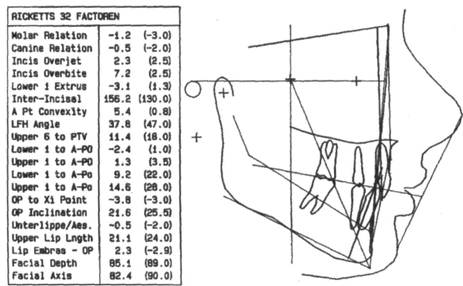

Телерентгенография. Этот метод рентгенологического исследования применяют для изучения строения лицевого скелета, его роста, уточнения диагноза и прогноза орто-донтического лечения, а также для выявления изменений, происходящих в процессе лечения. Телерентгенографию проводят в боковой и прямой проекциях с расстояния 1,5 м. Голову обследуемого фиксируют с помощью цефалостата различных конструкций, применение которых обеспечивает получение идентичных снимков (рис. 13.28).

челюстной системы в трансверсаль-ном направлении, в боковой проекции — в сагиттальном и трансвер-сальном направлениях. На ТРГ видны кости лицевого и мозгового черепа и контуры мягких тканей, что дает возможность изучить их взаимоотношения (рис. 13.29).

Для расшифровки ТРГ снимок помещают на экран негатоскопа, к

| Рис. 13.28. Телерентгенограмма головы, выполненная в боковой проекции. |

Рис. 13.29. Скопированная телерентгенограмма головы.

нему прикрепляют кальку, на которую переносят изображение.

ТРГ по методу Шварца позволяет наиболее полно изучить размер и положение челюстных костей. Пользуясь этим методом, можно провести краниометрические, гна-тометрические и профилометриче-ские измерения. С помощью краниометрии определяют: 1) расположение челюстей в сагиттальном и вертикальном направлениях по отношению к плоскости передней части основания черепа; 2) расположение ВНЧС по отношению к плоскости передней части основания черепа; 3) длину передней части основания черепной ямки.

Для анализа ТРГ используют следующие точки плоскости:

А — субспинальную точку Downs, наиболее глубокую на переднем контуре апикального базиса верхней челюсти;

В — супраментальную точку

Downs, наиболее дистально расположенную на переднем

контуре апикального базиса нижней челюсти;

Se — на середине входа в турецкое седло;

N — на передневерхнем крае но-солобного шва в сагиттальной плоскости;

Ог — наиболее низко расположенную точку нижнего края орбиты;

Go — точку угла нижней челюсти в месте пересечения его с биссектрисой угла, образованного касательными по нижнему краю тела и заднему краю ветви нижней челюсти;

С — самую верхнюю точку на контуре головки нижней челюсти;

Me — наиболее выступающую точку нижнего контура подбородочного отдела;

N — точку на коже, образующуюся при пересечении с продолжением линии N—Se;

Sna — переднюю носовую ость;

Snp — заднюю носовую ость;

Pg — самую переднюю точку подбородочного выступа;

NSe — плоскость переднего отдела основания черепа (ее проводят через точки N и Se);

SpP — плоскость основания верхней челюсти (проходит через точки Sna и Snp);

Рп — носовая вертикаль, которую проводят перпендикулярно к плоскости NSe через кожную точку п;

MP — плоскость основания нижней челюсти.

На ТРГ отделяют краниальную часть черепа от гнатической плоскости верхней челюсти (SpP).

Варианты расположения челюстей определяют по лицевому, инклина-ционному углу и углу горизонтали:

1) лицевой угол F образуется при

пересечении линий N—Se и N—А (внутренний нижний угол). Его величина характеризует расположение верхней челюсти по отношению к основанию черепа в сагиттальном направлении. Угол меньше нормы характерен для ретрогнатии, больше нормы — для прогнатии; если он находится в пределах нормы, говорят о нормогнатии;

2) угол горизонтали Н образуется при пересечении линии Н (горизонтальная линия) и Рп (внутренний верхний угол) и определяет положение суставной головки нижней челюсти по отношению к основанию черепа, что влияет на форму профиля лица;

3) инклинационный угол J образуется при пересечении линий Рп и SpP (внутренний верхний угол). Если угол J больше средней величины, то челюсти наклонены вперед, что Шварц назвал антеинкли-нацией. Если угол меньше средней величины, то челюсти отклонены назад. Такое положение челюстей называется ретроинклинацией.

Гнатометрический метод (по Шварцу) позволяет:

• определить аномалию, развившуюся в результате несоответствия размеров челюстей (длины тела челюсти, высоты ветвей нижней челюсти), аномалии положения зубов и формы альвеолярного отростка;

• выявить влияние размеров и положения челюсти, а также аномалии зубов на форму профиля лица;

• определить индивидуальную форму длины тела челюстей и отклонения в размерах.

Наиболее важные параметры гна-тометрии:

1) базальный угол В — угол наклона основания челюстей друг к другу (SpP — MP), характеризующий вертикальное положение челюстей;

2) длину тела нижней челюсти МТ измеряют по плоскости MP от проекции точки Pg на MP до точки пересечения ее с касательной к ветви нижней челюсти;

3) высоту ветвей МТ измеряют по касательной к заднему краю ветви от точки пересечения с плоскостью MP до проекции точки С на касательной;

4) нижнечелюстной угол G измеряют между линиями МТ] и МТ2, т.е. между касательными к нижнему краю нижней челюсти и задней поверхности ее ветвей;

5) длину верхней челюсти измеряют от точки пересечения перпендикуляра, опущенного из точки А на SpP (точка А'), до точки Sn.

Средние индивидуальные нормативы по Шварцу:

1) длина тела нижней челюсти при ее нормальном развитии равна длине основания передней черепной ямки (расстояние N — Se) плюс 3 мм;

2) длина верхней челюсти по отношению к длине переднего отдела основания черепа составляет 7:10;

3) длина тела нижней челюсти соотносится с длиной ее ветвей как 7:5.